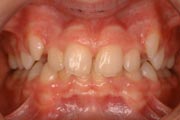

Crowding

Before